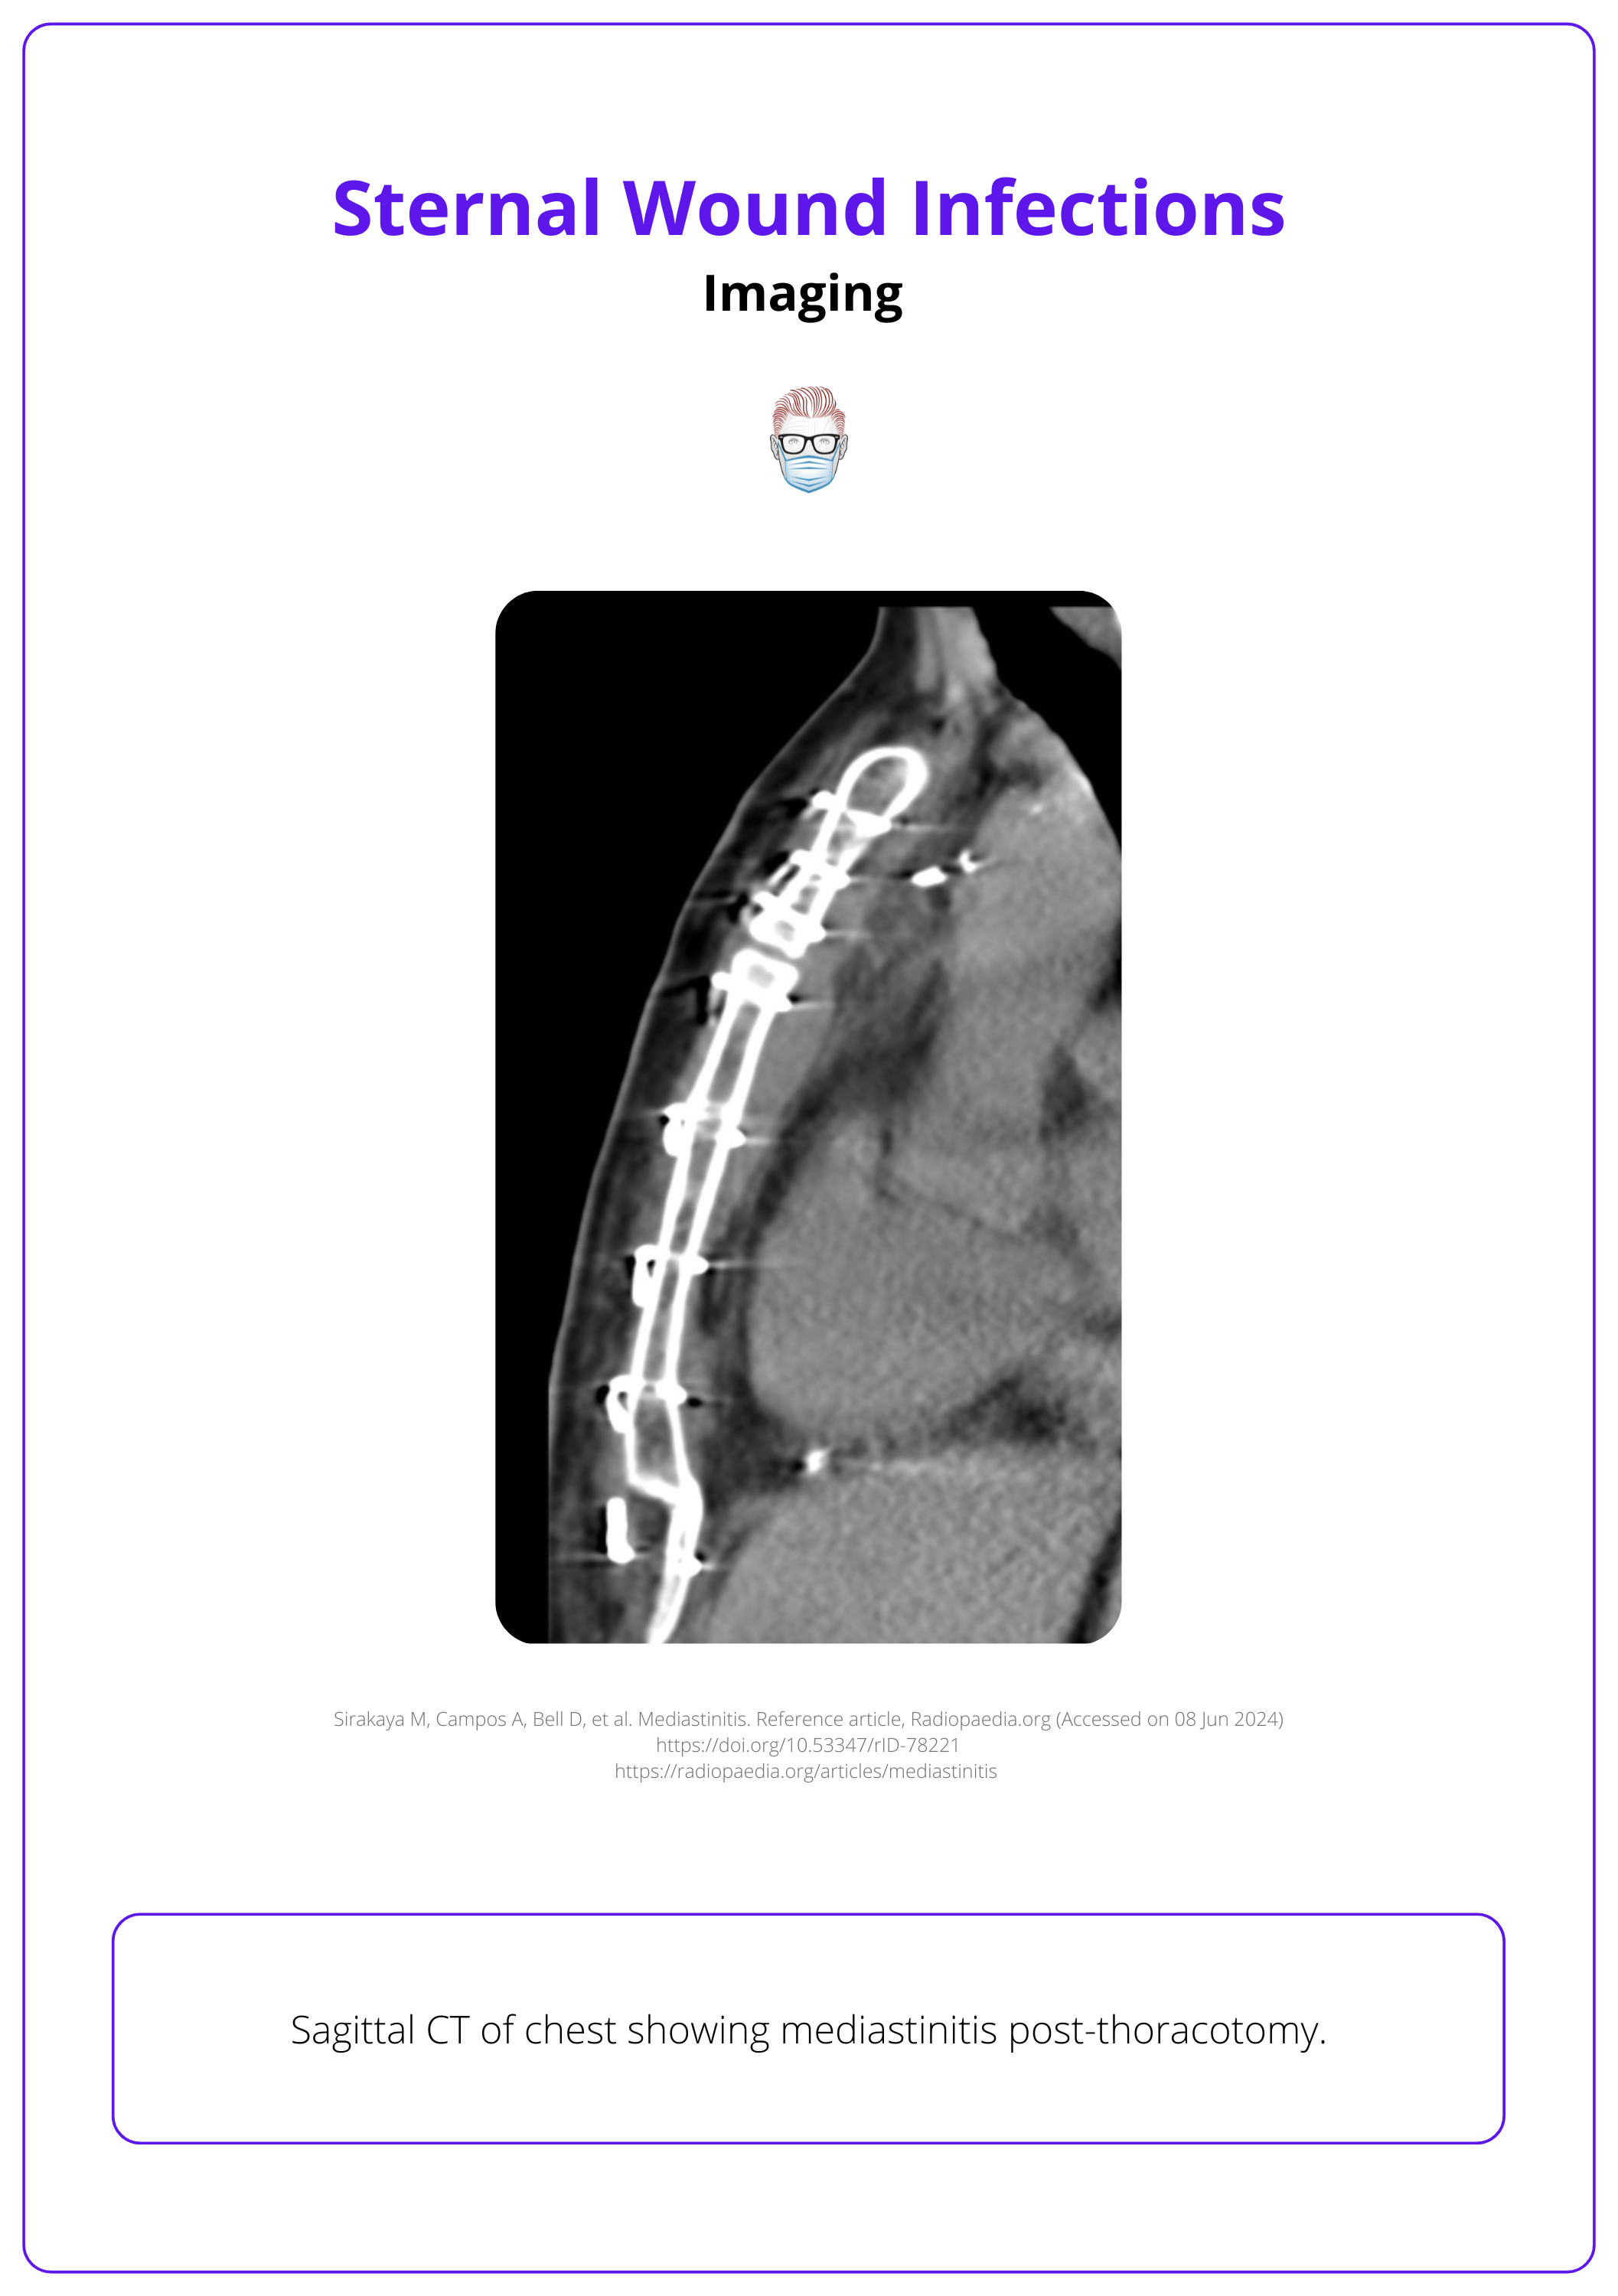

- CXR: Mediastinal widening, air-fluid level, pneumomediastinum, pleural effusion.

- CT chest: Assess dehiscence depth and identify fluid collections, abscesses, air pockets, extension into adjacent structures, pleural or pericardial fluid, adenopathy, and parenchymal or sternal abnormalities.